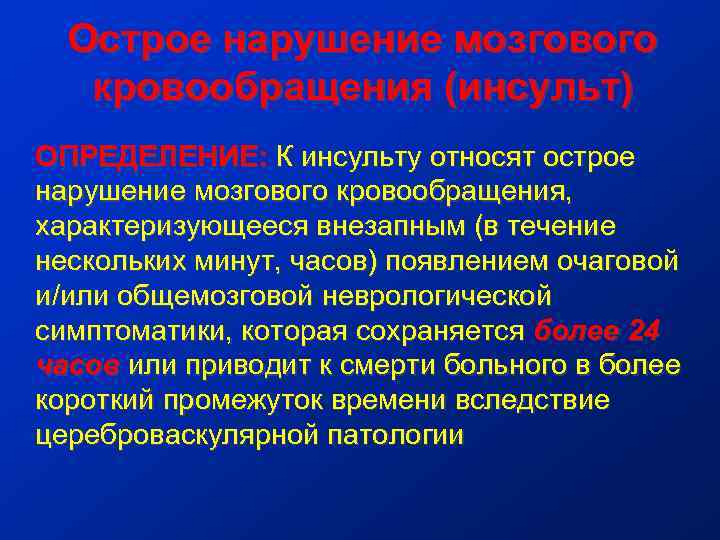

Пирамидная симптоматика в неврологии: ключевые аспекты